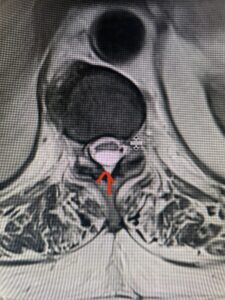

Fig: 2b Axial T2-weighted cervical MRI demonstrating spinal cord compression from C4-5 herniated disc (red arrow)